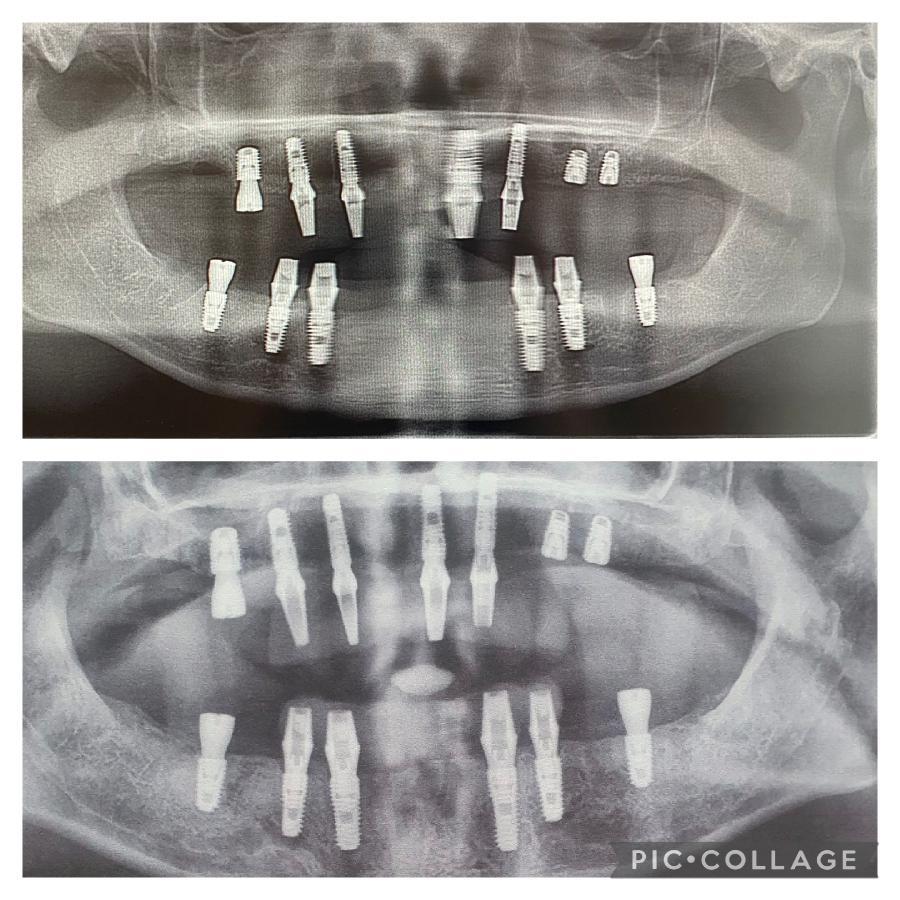

O femeie s-a dus în Turcia să-și facă dantura pe bani puțini. A fost desfigurată și suferă de dureri imposibile

Leanne, după intervenția din Turcia FOTO: Profimedia Images